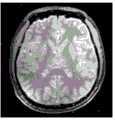

图12A至图41C是根据本发明的一些实施例的患者大脑的示例性检测结果。所述检测结果是基于具有与本发明公开的MR脉冲序列1000相似配置的MR脉冲序列和此处描述的示例性方法生成的。12A-41C are exemplary examination results of a patient's brain according to some embodiments of the present invention. The detection results are generated based on an MR pulse sequence having a configuration similar to the

图12A到图17C是大脑的基本图像。图12A至图12C分别是大脑冠状面、矢状面和横切面的T1加权图像。图13A至图13C分别是大脑冠状面、矢状面和横切面的局部放电加权图像。图14A至图14C分别是大脑冠状面、矢状面和横切面的T2*加权图像。图15A至图15C分别是大脑冠状面、矢状面和横切面的相位图像。图16A至图16C分别是大脑冠状面、矢状面和横切面的相位对比MRA图像,其中图16A至图16C中的相位对比MRA图像是采用包括正FE模块的MR脉冲序列产生的。图17A至图17C分别是大脑冠状面、矢状面和横切面的相位对比MRA图像,其中图17A至图17C中的相位对比MRA图像是采用包括负FE模块的MR脉冲序列生成的。图16A至图17C中的每个图像可以是包括相位信息的相位图像,并且其对应于包括相位信息和幅度信息的复合图像。Figures 12A to 17C are basic images of the brain. 12A to 12C are T1-weighted images of the brain in coronal, sagittal and transverse planes, respectively. Figures 13A to 13C are partial discharge weighted images of the brain in coronal, sagittal and transverse planes, respectively. Figures 14A-14C are T2*-weighted images of the brain in coronal, sagittal and transverse planes, respectively. Figures 15A to 15C are phase images of the brain in coronal, sagittal and transverse planes, respectively. Figures 16A to 16C are phase contrast MRA images of the brain in coronal, sagittal and transverse planes, respectively, wherein the phase contrast MRA images in Figures 16A to 16C were generated using an MR pulse sequence including a positive FE module. Figures 17A to 17C are phase-contrast MRA images of the brain in the coronal, sagittal and transverse planes, respectively, wherein the phase-contrast MRA images in Figures 17A to 17C were generated using an MR pulse sequence including a negative FE module. Each image in FIGS. 16A to 17C may be a phase image including phase information, and it corresponds to a composite image including phase information and magnitude information.